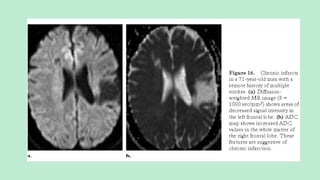

CHRONIC INFARCTS

Also called post infarction encephalomalacia.

NECT:

Sharply well-delineated wedge shaped hypodense area

that involves both GWM and is confined to a specific vascular

territory.

Features of volume loss are evident.

Depression in function, metabolism, and perfusion affecting a

cerebellar hemisphere occurring as a result of a contralateral focal

supratentorial infarct (cerebellar diachisis)

MRI:

Cystic encephalomalacia with CSF equivalent signal intensity

on all sequences.

DWI shows increased diffusivity and hyperintense on ADC.